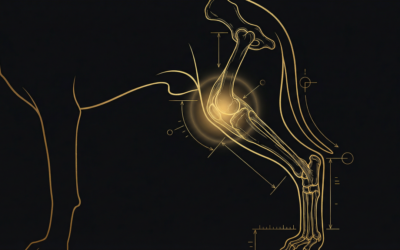

犬のパテラ(膝蓋骨脱臼)をトイプードル・チワワなど小型犬オーナー向けに徹底解説。原因・症状・グレードI〜IVの違い・保存療法と手術の選び方まで、獣医学論文をもとにわかりやすく紹介します。

「固有受容感覚」という言葉をご存知ですか?これは体の位置・動き・バランスを感知す…